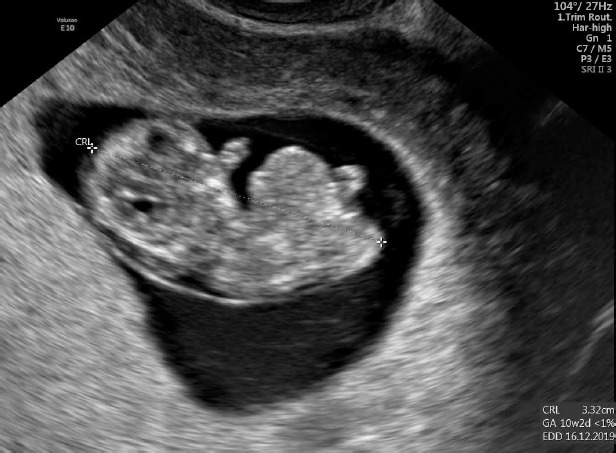

A thirty-three-year-old pregnant woman in her second pregnancy (the first pregnancy was unsuccessful – miscarriage at week 8 of pregnancy), visited a gynecologist for a routine check-up at week 12 of pregnancy, during which developmental disorders were found in the anterior chest cavity and abdominal walls. The woman was healthy, denied having chronic diseases, and was taking folic acid and vitamin preparations for pregnant women. The patient also denied the existence of any infections at an early stage of pregnancy. The woman was referred to the Laboratory of Prenatal Research, where, during prenatal ultrasound examination, the fetus was diagnosed with a complex defect of the skin and division of the body’s cavities in the form of pentalogy of Cantrell. The fetus was diagnosed with umbilical cord omphalocele (Figure 1), diaphragmatic hernia with diaphragmatic defect, sternal defect, ectopic heart and pericardial defect (Figures 2-3).

The swelling of the entire fetus was visualized – NT 5 mm (Figure 6) and reverse flow in the ductus venosus (Figure 7).